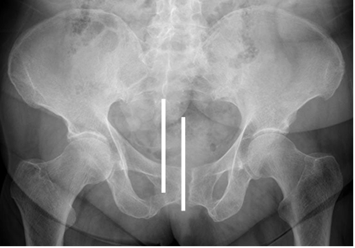

Una Rx de adecuada calidad no debe estar rotada, (Alineación del cóccix con la sínfisis púbica), tener simetría de los agujeros obturadores y una adecuada inclinación pélvica. (Distancia entre borde superior de la sínfisis y extremo del cóccix entre 1 y 3 cm). (4). (Fig 7 y 8).

Fig 7. Técnica radiológica.

Rx AP. Rotación lateral de la pelvis.